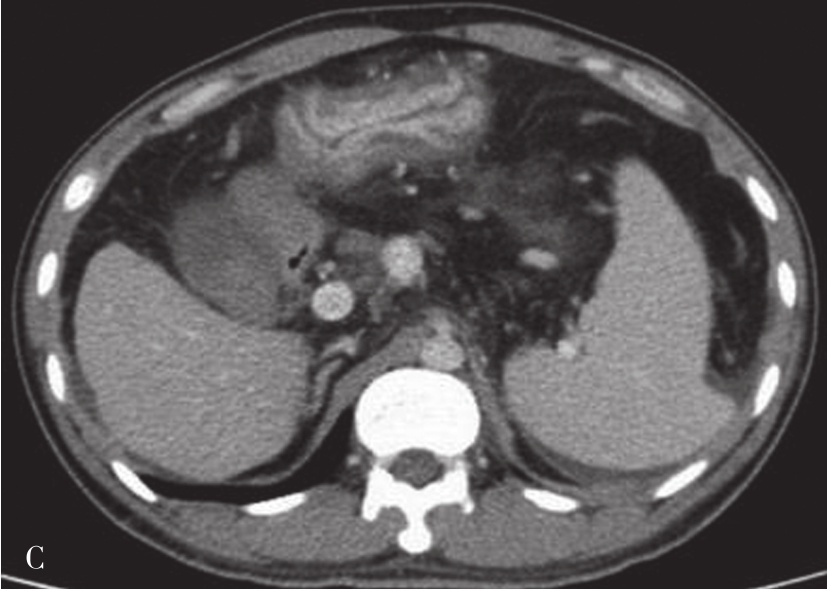

(3)肝8段划分法(图5-21-35):

Couinaud根据门静脉及肝静脉的分布将肝脏分为8段,门静脉分布于肝段内,肝静脉分布于肝段间。8分段法是临床外科和影像最为常用的分段法。以肝中静脉为界分为左、右半肝;以肝左静脉为界将左半肝分为左内(Ⅳ段)和左外叶(Ⅱ段+Ⅲ段);左外叶以门静脉左支为界水平分为上(Ⅱ段)下(Ⅲ段)两段;以肝右静脉为界分右半肝为前叶(Ⅷ段+Ⅴ段)和后叶(Ⅵ段+Ⅶ段);以门静脉右支为界将右肝横向分为上下两段分别为右前上段(Ⅷ段)、右前下段(Ⅴ段),右后下段(Ⅵ)和右后上段(Ⅶ段);肝尾状叶为单独一段(Ⅰ段)。

图5-21-35 肝8段划分法示意图